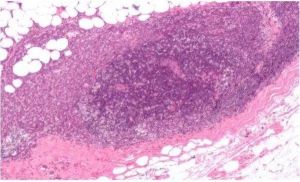

急性乳腺炎的發病過程大體經歷乳管炎、乳腺炎和乳房炎3個階段。細菌侵入乳管,上行至腺小葉,停留在滯積的乳汁中生長繁殖,導致乳管的急性炎症。繼而擴散至乳腺實質,引起實質性乳腺炎。細菌亦可從乳頭皸裂的上皮破損處沿著淋巴管到乳腺間質內,引致間質性乳腺炎。此階段未能及時治療,或治療不當,炎症即向乳腺實質以外的脂肪和纖維組織擴散,導致急性乳房炎。炎症局限,組織壞死、液化,大小不等的感染灶相互融合形成乳房膿腫;若膿腫穿破到乳房後間隙的疏鬆結締組織內時,則形成乳房後膿腫。